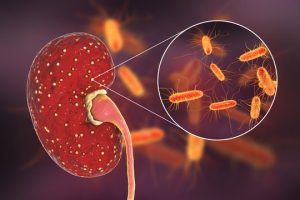

Cầu thận là nơi thực hiện việc lọc máu của cơ thể chúng ta. Cầu thận giữ lại các chất dinh dưỡng và điện giải cần thiết, đồng thời loại bỏ đi các chất gây nguy hại cho cơ thể qua một hệ thống màng lọc. Khi tổn thương tại cầu thận, hệ thống lọc này hoạt động không hiệu quả, từ đó dẫn đến thất thoát cả các chất dinh dưỡng của cơ thể mà bình thường sẽ được giữ lại. Trong hội chứng thận hư, việc tổn thương cầu thận đã làm thất thoát các protein trong máu, khiến protein xuất hiện với nồng độ cao trong nước tiểu.

Hội chứng thận hư là một hội chứng lâm sàng và sinh hóa, xuất hiện khi có tổn thương ở cầu thận do nhiều tình trạng bệnh lý khác nhau gây nên, đặc trưng bởi phù, protein trong nước tiểu cao, protein trong máu giảm, rối loạn lipid máu và có thể tiểu ra mỡ. (Theo định nghĩa Hội chứng thận hư ở người trưởng thành của Bộ Y tế, 2015).